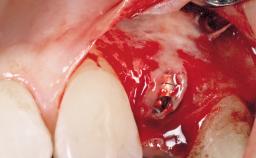

Immediate Placement of an Implant in a Maxillary Right Central Incisor Site

A 30-year-old female patient was referred to the office for the treatment of tooth 11. Her chief concern at the initial visit was to inquire, “Why is my tooth pink?” Upon clinical examination, it was determined that tooth 11 had a previous history of trauma and that the clinical crown had become noticeably pink in color as a result of internal resorption. This diagnosis was confirmed radiographically, indicating a large radiolucency involving the central and distal portions of the clinical crown. It was determined that restoration of this tooth was not possible, and that extraction was indicated. The presence of a mid-line diastema, which the patient wanted to reproduce, directed the treatment plan for tooth replacement utilizing a dental implant.